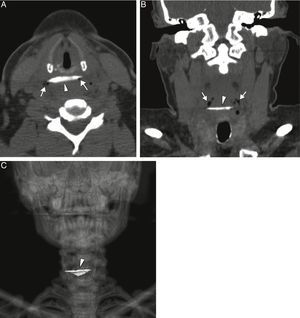

Una mujer de 43 años de edad llegó a nuestro departamento de urgencias, habiendo ingerido un hueso de pollo. Sus síntomas clínicos eran babeo ligero y sangre en la saliva. Se sometió al paciente a un examen de fibra óptica, que reveló un hueso como cuerpo extraño en la mucosa del esófago proximal, que parecía estar causando una perforación parcial (fig. 1). Una tomografía computarizada confirmó la presencia de un cuerpo extraño con forma de hueso, con bordes puntiagudos a la altura del esófago proximal, con perforación limitada (fig. 2A-C). Se realizó una extirpación endoscópica urgente del cuerpo extraño, sin complicaciones, y se confirmó que el objeto era un pedazo de hueso de pollo afilado (fig. 3).

A) Imágenes axial y B) coronal de la tomografía computarizada que muestran el cuerpo extraño con forma de hueso (punta de flecha) a la altura del esófago proximal, con pequeñas burbujas de aire en el tejido blando (flechas), como indicación de una perforación limitada. C) La reconstrucción de imagen del renderizado de volumen 3D de la tomografía computarizada coronal del cuerpo extraño con forma de hueso (punta de flecha).